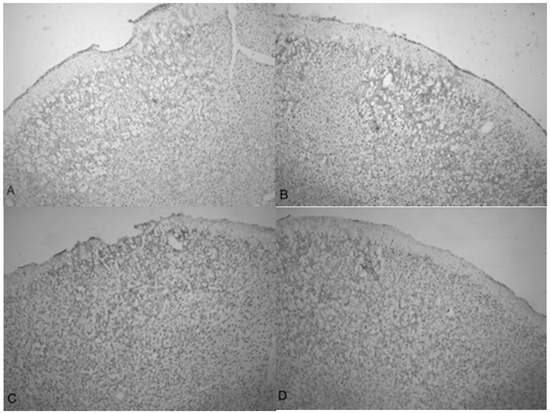

Microphotographs of cresyl violet stained tissue from 3.4 bar TBI treatment (Figure 4A,C) show indentation and fragmentation of the cortex exactly where the acoustic wave was administered to two separate rats. The opposing panels (Figure 4B,D) show intact, unaffected tissue in the contralateral cortex at the same stereologic orientation (approximately +3.0 anterior to bregma). In addition, the cells in Figure 4A,C appeared to be more sparsely distributed in the damaged region, suggesting neurodegeneration and disruption of neural pathways. Similar histological profiles were observed with 4.2 bar sections.

Figure 5A shows the TBI-targeted left frontal cortex 10 days after 5.0 bar acoustic wave treatment. Note the severely damaged cortex compared to 3.4 bar treatment cortex (see Figure 4A,C). While the histology from the 3.4 bar treatment revealed moderate impairment of the dura mater and the arachnoid layer, the 5.0 bar treatments showed significantly more damage to post-TBI tissue that ranges well beyond the pia mater. The intact contralateral cortex showed no damage (Figure 5B). Also, no additional damage was detected in any other brain region of the TBI-treated rats, including the hippocampus.

A side-by-side comparison of all four treatments is shown in Figure 6. An intact, uninjured cortex revealed no detectable damage (Figure 6A). Slight damage of the outer cortex that does not penetrate beyond the pia mater is seen in the 3.4 bar treatment (Figure 6B). The injury from the 4.2 bar treatment is much more significant than that of the 3.4 bar, penetrating beyond the pia mater and reaching cortical neurons (Figure 6C). The depth of the 4.2 bar injury can be compared to that of the 5.0 bar injury (Figure 6D). The 5.0 bar treatment is much more pervasive and penetrates even deeper into the cortex. The clearer space within the marked region (Figure 6D) clearly shows neuronal cell death.

Figure 4. Microphotographs show the tissue from the frontal cortex visualized with cresyl violet from 60 day-old Han-Wistar rats, 10 days post-injury. Images indicate the damage from the acoustic wave 3.4 bar TBI targeted left frontal cortex as shown in the left panels (A,C) and compared with the contralateral, unaffected right frontal cortex (B,D) from the matching animals. Panels (A,C) show indentation and fragmentation of the cortex where TBI was administered while panels (B,D) show intact, unaffected tissue. In addition, the cells in A and C are more sparsely detected, suggesting neurodegeneration and disruption of neural pathways in these animals. All photomicrographs were taken at 40× magnification.

Figure 6. Photomicrographs taken of the frontal cortex showing the overall depth of injury and due to the penetration of acoustic waves: the control (0 bar), 3.4, 4.2 and 5.0 bar TBI, respectively of Han-Wistar rats, ten days post-injury. Image (A) shows no damage from an untreated, control rat (0 bar). Image (B) shows slight damage to the outer cortex (3.4 bar). Images (C,D) show the deeper penetrating impact delivered by the 4.2 and 5.0 bar. The dotted lines show examples of the infarct boundaries traced by locating the perimeter of condensed dark cells used to calculate the expanse of the area damaged. All images were taken at 40× magnification.